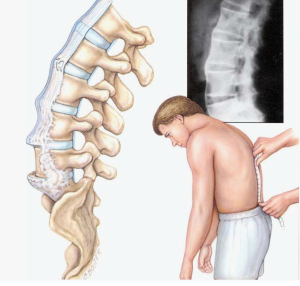

Анкилозирующий спондилит (АС) — хроническое воспалительное заболевание, сопровождающееся формированием ригидных деформаций позвоночника и нарушением сагиттального баланса

Прогрессирование АС приводит к формированию кифотической деформации и увеличению подбородочно-бровного вертикального угла (CVBA), что обусловливает функциональные нарушения у 30 % пациентов [2]. Основная цель хирургии при АС — коррекция сагиттального дисбаланса, восстановление горизонтального взгляда, уменьшение болевого синдрома и улучшение функционального статуса.

— выраженная кифосколиотическая деформация («поза просителя») (рис. 1, а);

— клиновидная деформация Th12, L1 позвонков с формированием спондилита Андерсена на этом уровне и кифосколиотической деформацией позвоночного столба (рис. 1, б);